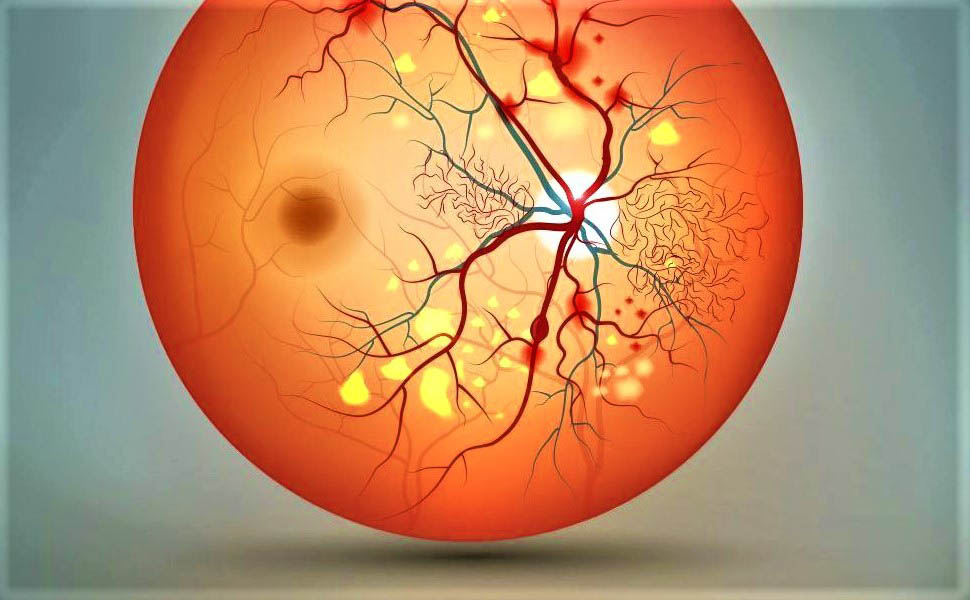

Хроническая окклюзия артерий: причины, симптомы и лечение